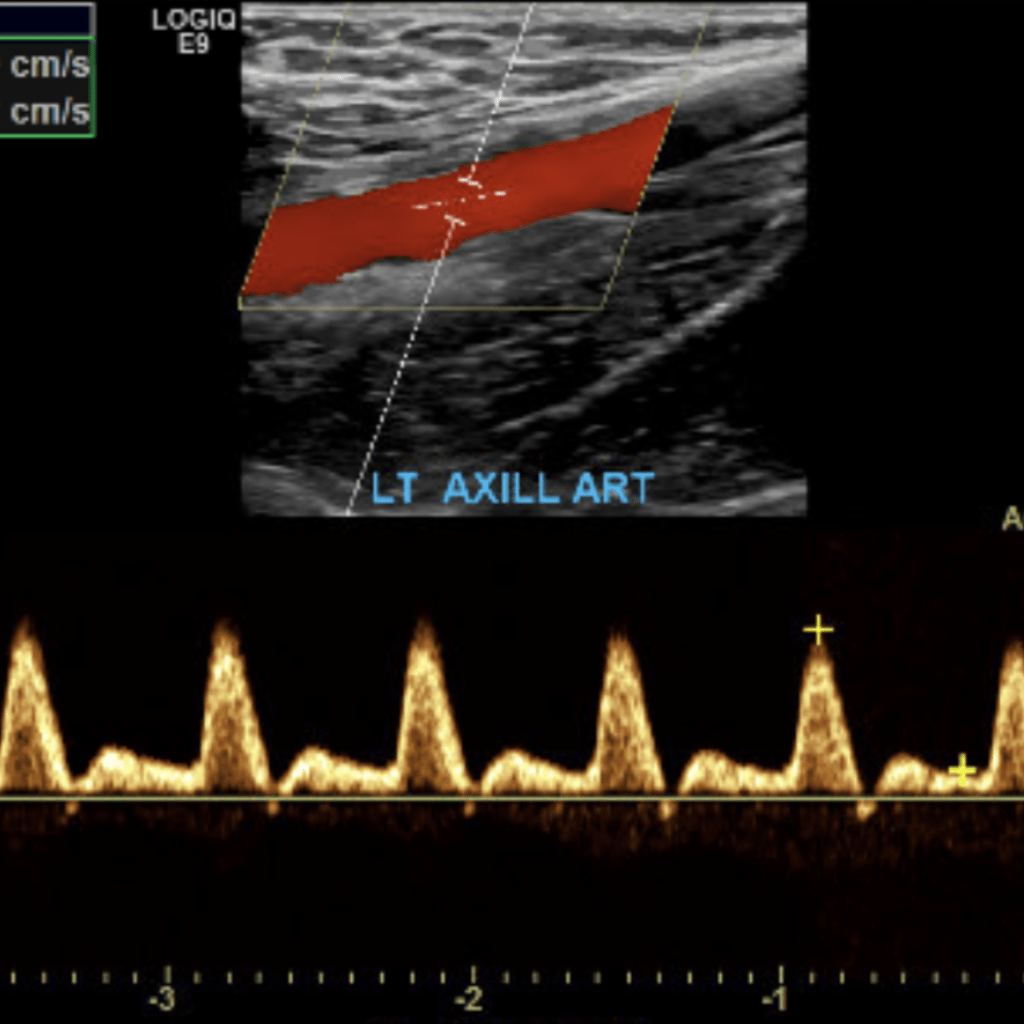

The subclavian artery arises from the brachiocephalic artery on the right and off of the aortic arch on the left. This artery further divides into the axillary, brachial, radial, ulnar, palmar and digital arteries respectively.